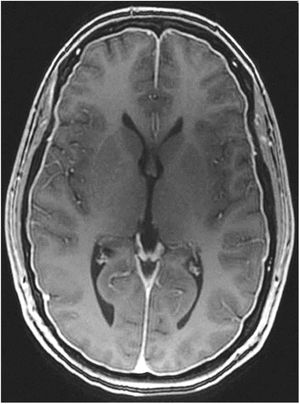

Gadolinium-enhanced brain MRI: this is the neuroimaging study of choice to confirm clinical suspicion of SIH; results are diagnostic in 80% of cases.49 MRI results from more than 2000 patients with SIH have been reported; the signs described are summarised in Table 10.48,49 Diffuse, homogeneous pachymeningeal enhancement is the most frequent radiological sign (Fig. 2). However, evaluation of these signs requires training, to prevent conclusions from being drawn arbitrarily. This has led to the development of such instruments as the Bern score (Table 11).59,60 MRI findings vary according to disease progression time.61

Table 10.Magnetic resonance imaging signs of spontaneous intracranial hypotension.48,49

Diffuse pachymeningeal enhancement (73–80%), which is also observed on non-contrast FLAIR sequences in the majority of cases (Fig. 2)Extra-axial fluid collections (35–50%), hygromas in 60% of cases and haematomas in 40% (Fig. 4) Brain sagging disproportionate to the size of the fluid collections (43%). Images may display the following signs:Ventricular collapseBowing of the optic chiasm Flattening of the pons against the clivus with obliteration of the pontine cistern Drooping of the corpus callosumDescent of the cerebellar tonsilsVenous engorgement (57%) Enlarged pituitary gland (38%)Intraventricular pneumocephalus (Fig. 5) in cases of iatrogenic SIHDecreased optic nerve diameter and thickness on coronal T2-weighted sequences, also detectable with transorbital ultrasound SIH: spontaneous intracranial hypotension.

Figure 2.Diffuse, homogeneous pachymeningeal enhancement in the brain MRI study of a 42-year-old woman with spontaneous intracranial hypotension confirmed with cerebrospinal fluid manometry in a lumbar puncture procedure. Courtesy of Dr. Belvís. Neurology department, Hospital de la Santa Creu i Sant Pau. Barcelona.